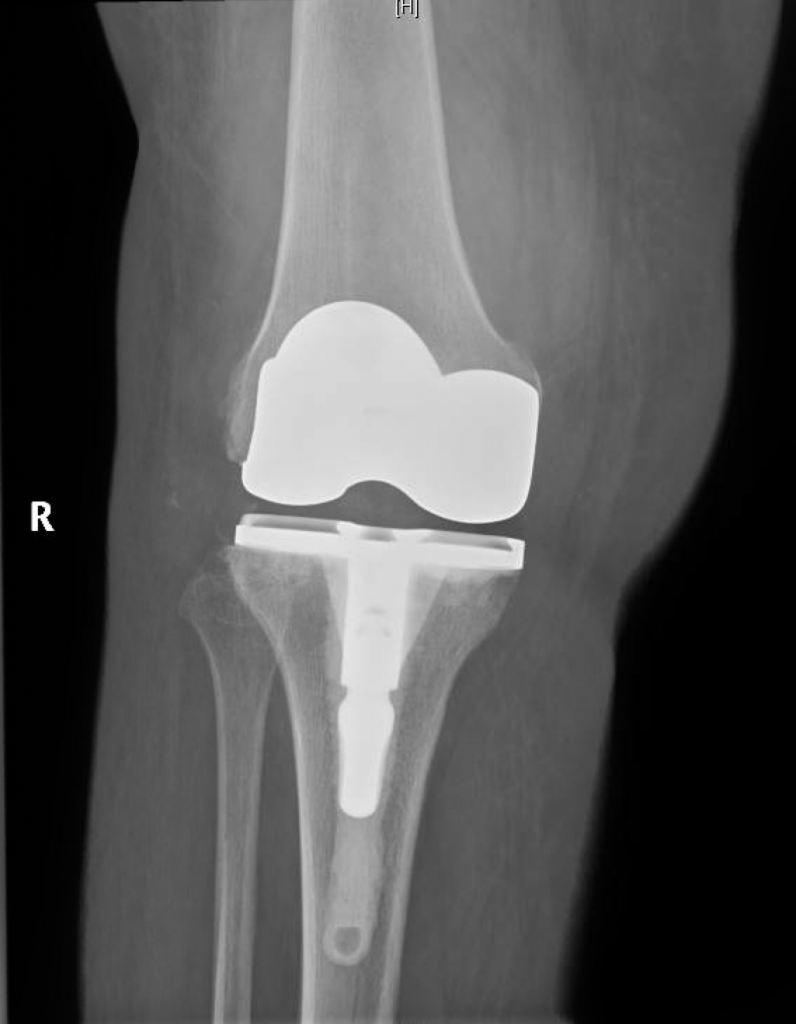

She underwent reconstructive total knee replacement, which corrected her deformity completely.

At 3 months after surgery, the patient was able to walk without pain and uses a cane for long distances only.